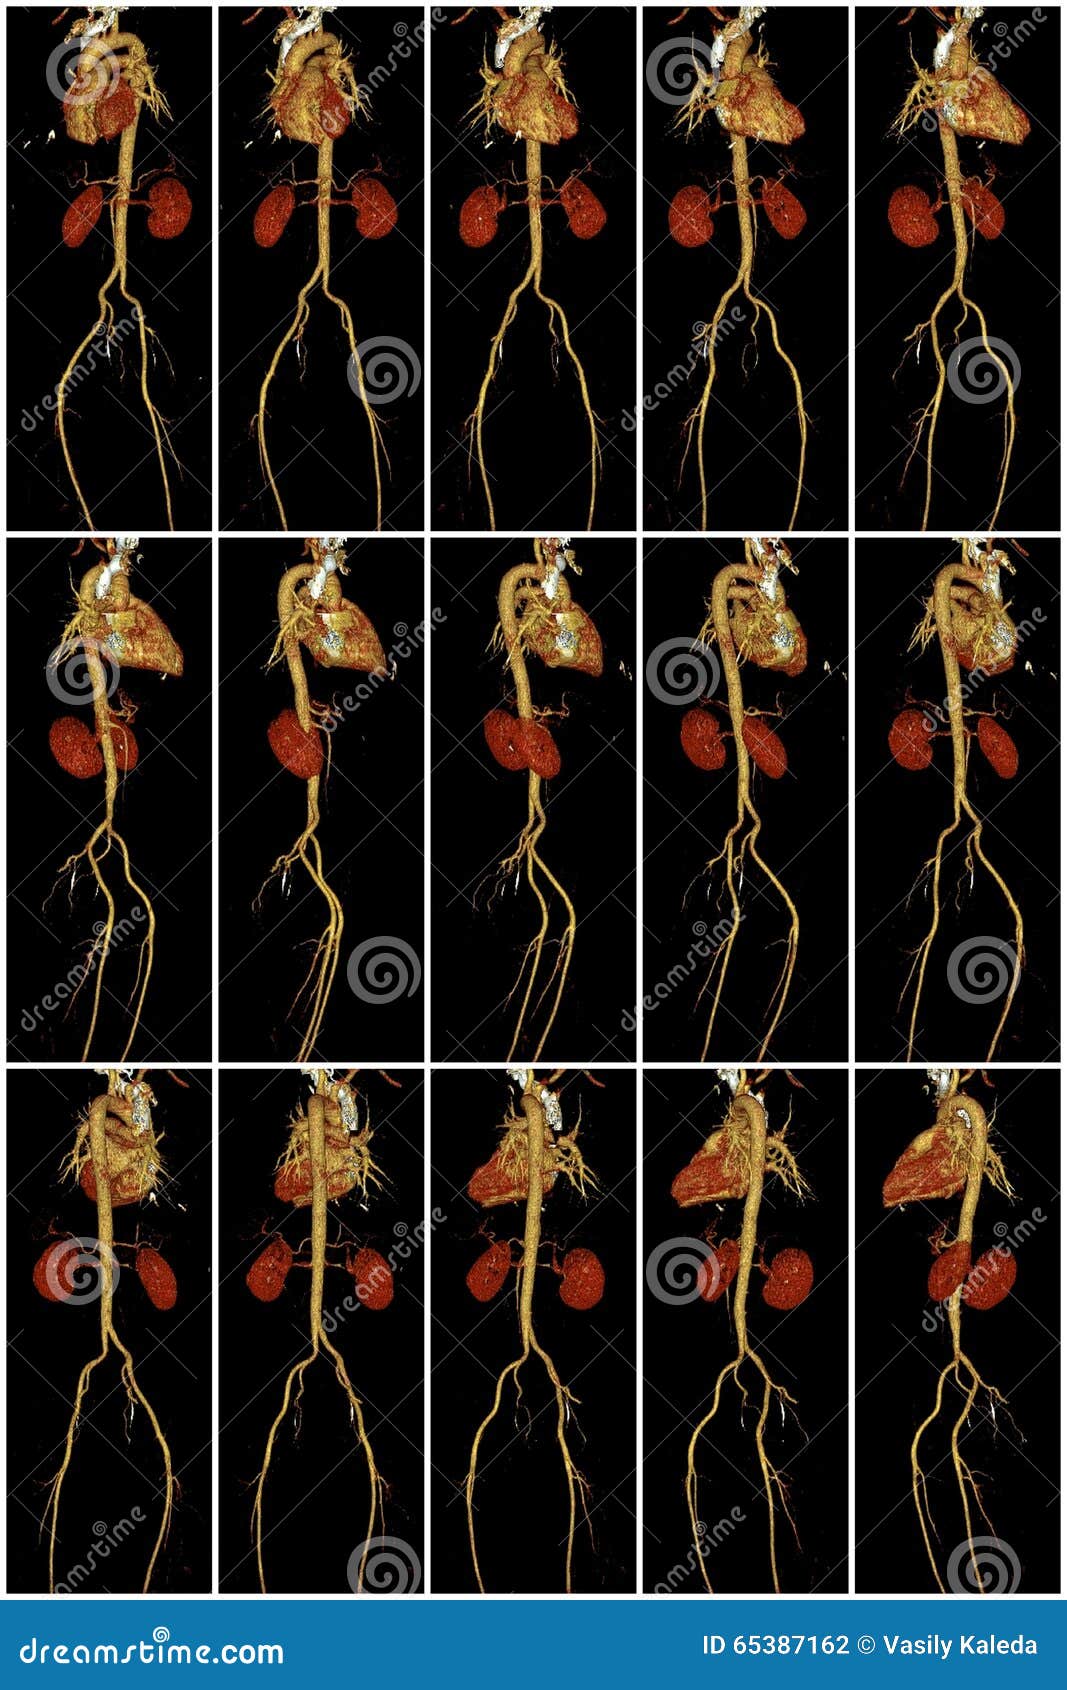

From www.dreamstime.com

Heart, Aorta and Kidneys on Computed Tomography Stock Photo Image of Heart Rentgen From the right to the left. The cardiac anatomy will be discussed in the order of normal blood flow: Last revised by yuranga weerakkody on 4 sep 2021. Left ventricular enlargement can be the result of a number of. Congestive heart failure (chf) is the result of insufficient output because of cardiac failure, high resistance in the circulation or fluid. Heart Rentgen.